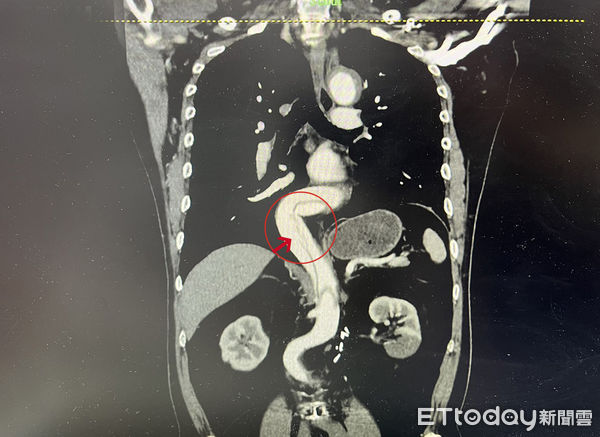

澄清医院中港院区急诊室主任郑清万表示,病患到院时腰背严重疼痛,左下肢发麻苍白,X光片检视,腰椎并无异常,但血压高达285/145mmHg,左右下肢血压相差达80 mmHg,高度怀疑是大血管的急症,立刻将病人转入急救区;经主动脉血管断层摄影,发现患者从胸大动脉、腹部动脉、左侧肾动脉,到左下肢髂动脉,一路破裂至少40公分长,血液撑裂血管内层,导致血管外层鼓涨成假腔,假腔内已积血约100cc,随时有破裂的可能,一旦大破裂,死亡率高达90%。

经确诊为主动脉破裂后,紧急会诊心脏血管外科,由另一名医生吴慧中接手治疗,经置放主动脉内的血管支架,并修补血管破裂,患者住院6天后,就康复出院。